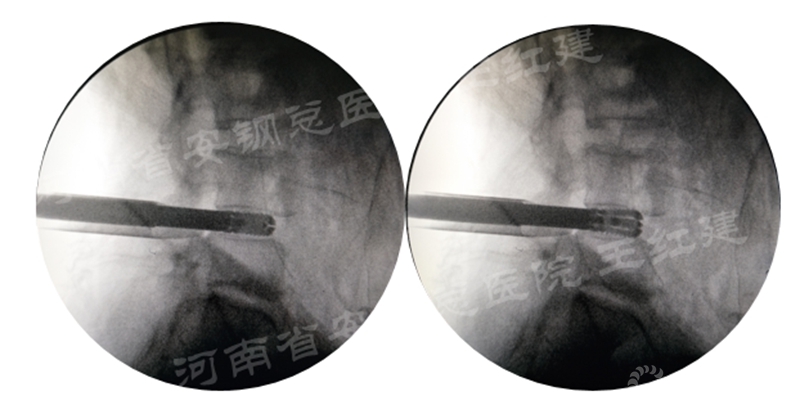

四、经皮螺钉技术固定

在固定的步骤可以先期进行经皮螺钉置入,再进行融合器的置入,进而实现充分固定。

椎弓根植入加压固定

手术步骤:先期经皮螺钉置入、再进行融合器的置入